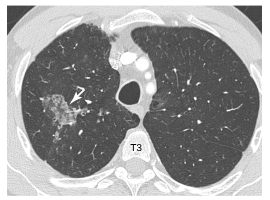

Fig. 92.1. Scanner thoracique avec injection de produit de contraste iodé.

Plage de « verre dépoli » du lobe supérieur droit (flèche) à contours géographiques correspondant à une zone d’hémorragie alvéolaire.

Source : CERF, CNEBMN, 2022.